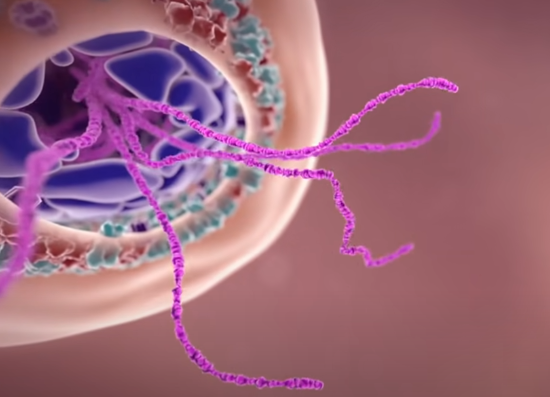

直到遇到合适的时机,它会脱去包膜,释放体内的 RNA。这里的 RNA 身兼两项任务,一是合成病毒蛋白质组件,二是复制 RNA 自身。

在第一项任务中,病毒会策反细胞里的核糖体来为自己服务。核糖体在细胞工厂的职责是制造蛋白质,但是现在,他会为病毒制造各种蛋白质组件,比如前面提到的刺突糖蛋白。

生产出的蛋白质组件会吸附在高尔基体生成的小泡表面,进而转运到细胞膜。

另一项任务中,病毒通过控制细胞体内的酶,重新复制自己的遗传物质 RNA 用于孕育新病毒。而且,这个过程会抑制细胞自身基因的表达,集合被感染细胞的资源全力为病毒生产材料。

最终,在细胞膜上会聚集大量的病毒蛋白质组件和 RNA。

一个全新装配的新冠状病毒会从细胞工厂被生成出来,他的使命是去感染另一个细胞。至此,这个不幸被病毒控制的细胞会完全沦陷,成为一个制造大量病毒的工厂。直到细胞工厂耗尽所有资源,病毒会果断抛弃它,寻找下一个健康细胞作为感染目标。